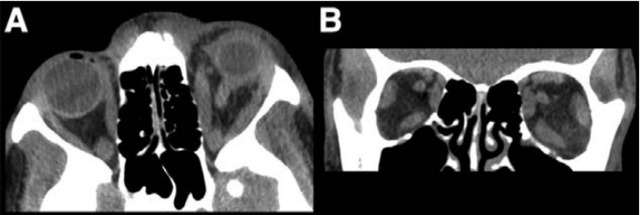

图 2 A 为患者 2 左眼水平直肌增大,图 2 B 为左侧所有直肌增大